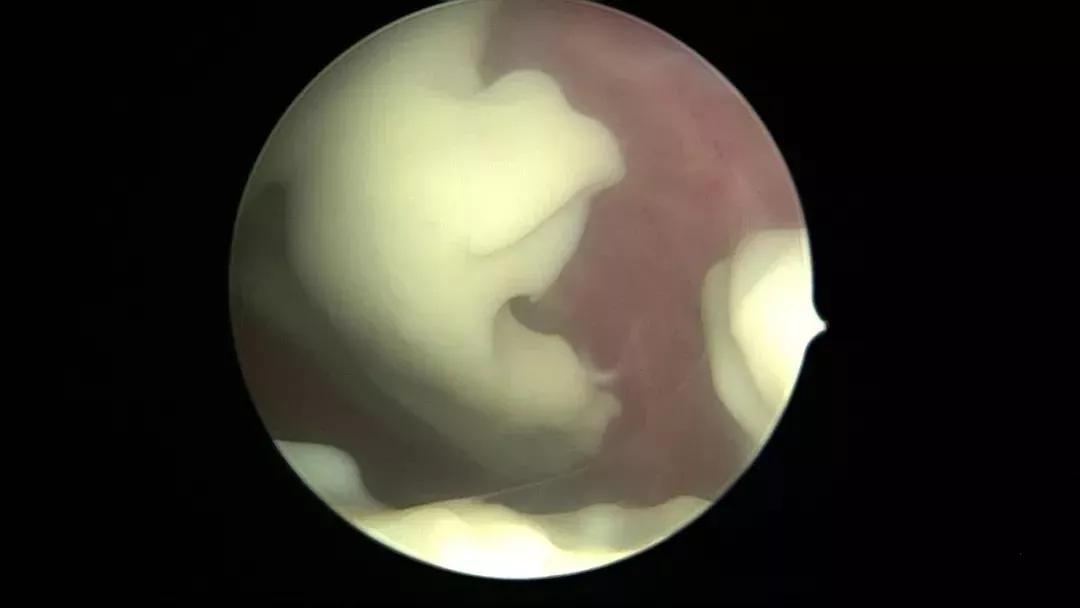

宫腔积脓所致黏连

宫腔积脓育龄期妇女少见,文献报道发病率0.1%~0.5%,在绝经后女性中发病率可高达13.6%。老年女性雌激素水平低,生殖器官萎缩,易充血破溃;缺乏定期月经冲刷及内膜修复功能,同时阴道乳酸杆菌减少,自净功能减弱,易引起上行感染;对宫腔感染疼痛敏感性降低,不适症状未及时就诊,延误病情;加之宫颈粘连、宫腔粘连、宫内包块、宫内节育器等导致宫腔分泌物引流不畅,易集聚感染,最终出现宫腔积脓。宫腔积脓典型感染症状少见,大部分病人没有任何临床症状,B超发现宫腔积液也缺乏特异性,因此宫腔积脓见到脓液之前很难确诊。